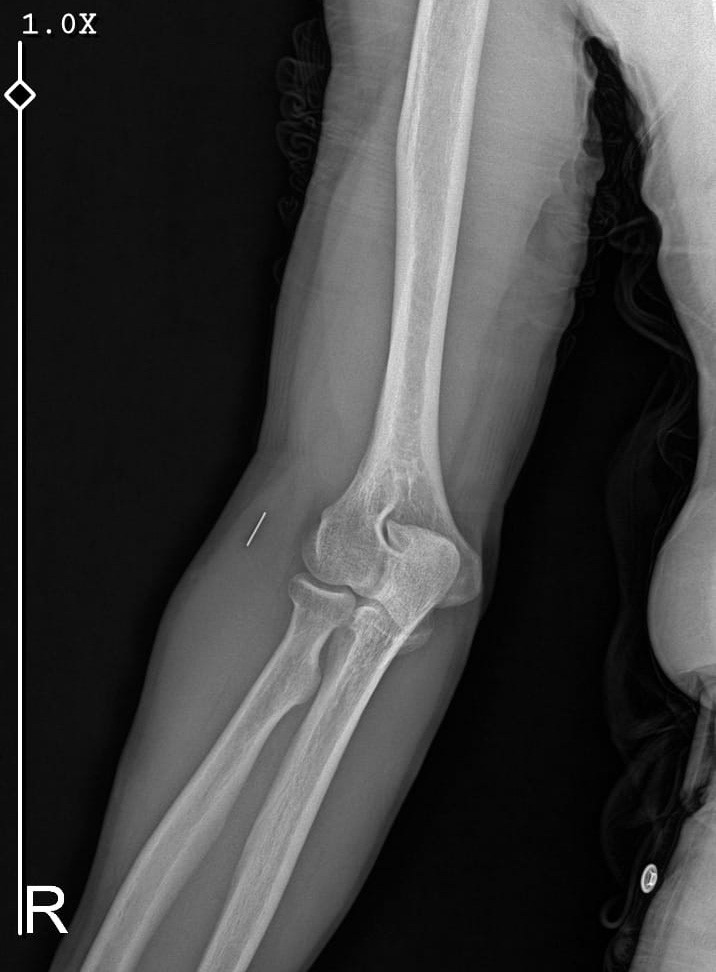

Öte yandan, ameliyatların ardından ağrıları devam eden Güleryüz’ün kolunda metal parça bulunduğu ve bu parçanın parmak bölgesinden dirseğe doğru ilerlediği öne sürüldü. Ayrıca, fabrikada temizlik personeli olarak çalışan Nurettin Güleryüz’ün hastane sürecinde işten çıkarıldığı da öğrenildi.